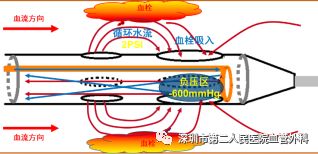

PMT是经皮机械血栓清除术,目前国内临床使用的主要是AngioJet Ultra 血栓清除系统,其原理是运用了流变学伯努利原理,能够有效清除血栓,迅速减轻血栓负荷,使症状快速获得缓解;快速开通血管,恢复血流,改善远端血供;减少平均住院时间,节省整体治疗费用。(图13-14)

图13 血栓被喷射水流击碎、被吸进导管并排出体外

图14 PMT手术治疗前后即刻效果